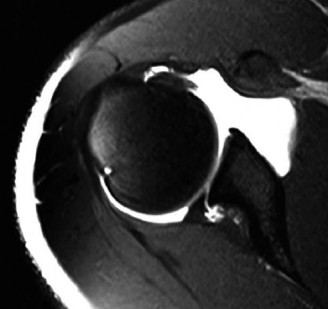

The correct answer is (B). An MRI showing a rotator cuff tear is considered diagnostic of a rotator cuff tear because of its high sensitivity, specificity, and accuracy. It has superb soft tissue imaging abilities (see Fig. 2–5). However, it should be noted that while MRI usually can differentiate between partial- and full-thickness rotator cuff tears, this varies with the power and accuracy of the MRI facility. This is also true with the ability of MRI to differentiate between partial-thickness rotator cuff tears and subacromial bursitis. An arthroscopy is needed for definitive differentiation of these pathologies.

Figure 2–5_Coronal oblique view MRI slice of a left shoulder. (Reproduced with permission from Smithius R and van de Woude HJ. Shoulder MR Anatomy: Normal Anatomy, Variants, and Checklist. _Radiology Assistant. April 2, 2012.)

MRI remains the most popular imaging modality for diagnosing rotator cuff tears. Normal rotator cuff tendon appears dark on both T1 and T2 sequences. Tears may be noted as being full-thickness, articular-sided, bursal-sided, or intrasubstance. They are visualized as a disruption in the regular contour of the tendon and increased signal intensity on T2 sequences. Occasionally, an MR arthrogram may provide additional information regarding a cuff tear, although this is not routinely ordered.

The correct answer is (D). T2 sequence causes most soft tissues, including muscle and tendon, to appear dark and inflammation, such as at the site of a tear, to appear bright. This means that if there is a rotator cuff tear, there will be a bright spot along the course of the dark rotator cuff tendon. This is easiest to pick out in the coronal plane because the tendon runs in this plane, allowing one to view the entire supraspinatus tendon and tear in one cut.